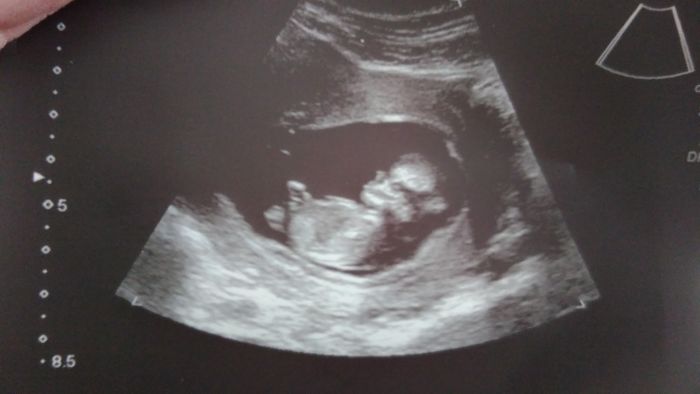

Hoj holky ja dnes kontrola creening,ultrazvuk paradni uplne sebou hazel,maval nam..podle utz vychazim na 12+1 a TP 30.10 ale moc tomu neverim..veliky okolo 6 cm a pry asi kluk ale ze nechce nic moc rikat takhle brzo..jinak me je uz dobre..zaludek uz jen citim ze tam neco roste..od zacatku tehu sem zhubla 3 kila..strasne malinko jim..jindy bych snedla celou porci a ted jen pulku :-) ono se to zase otoci :-)